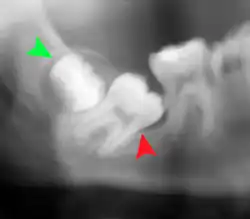

Coronectomy is a procedure where the crown of the impacted wisdom tooth is removed, but the roots are intentionally left in place. It is indicated when there is no disease of the dental pulp or infection around the crown of the tooth, and there is a high risk of inferior alveolar nerve injury.[32]

Coronectomy, while lessening the immediate risk to the inferior alveolar nerve function has its own complication rates and can result in repeated surgeries. Between 2.3% and 38.3% of roots loosen during the procedure and need to be removed and up to 4.9% of cases require reoperation due to persistent pain, root exposure or persistent infection. The roots have also been reported to migrate in 13.2% to 85.9% of cases.[32]